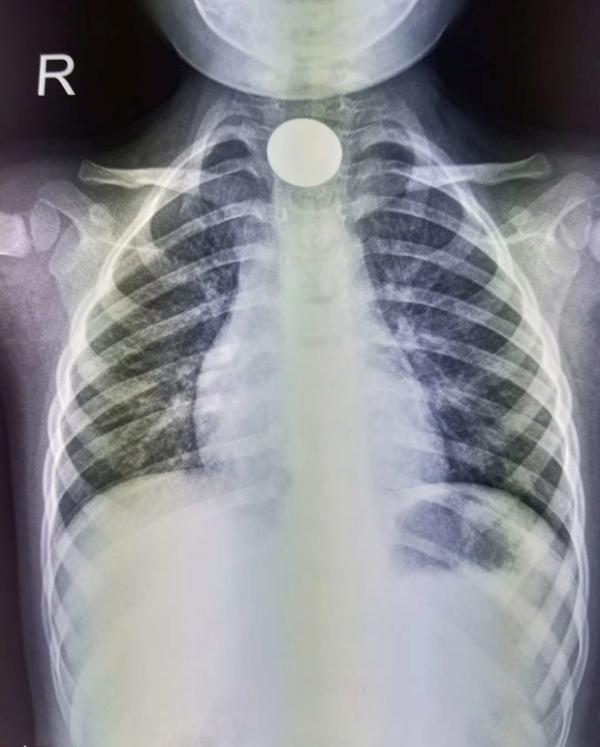

1、最常見的“急診玩具”——硬幣。

作為名副其實的“吞金獸”,硬幣一直是小朋友們的最愛,常年高居兒童呼吸道和消化道異物榜首。這主要是因為孩子的咽喉部保護性反射發育不完善,當孩子將硬幣、堅果、玻璃珠、紐扣電池、玩具零部件等這種體積小,且形狀圓頓的玩具含在嘴裡時,孩子的咽喉部不能有效阻擋異物。這類異物如果進入呼吸道,可引起呼吸困難或反覆肺部感染,從而出現氣促、發熱、咳嗽等症狀。若進入消化道,多可自行排出,但小部分可停留在消化道狹窄處,導致區域性粘膜損傷或消化道梗阻,甚至破裂穿孔,從而出現頑固性惡心、嘔吐、胸痛、腹痛、腹脹等症狀。